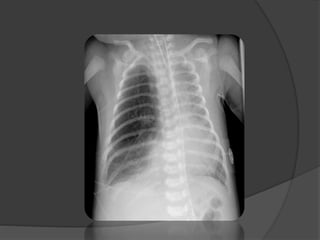

 La radiographie du thorax: Diagnostic (+)

Topographie

 Hyper clarté homogène compressive

 Trame vasculaire conservée mais grêle

 Signes de distension thoracique

 Hernie médiastinale + refoulement

controlatéral

 Pseudo-pneumothorax